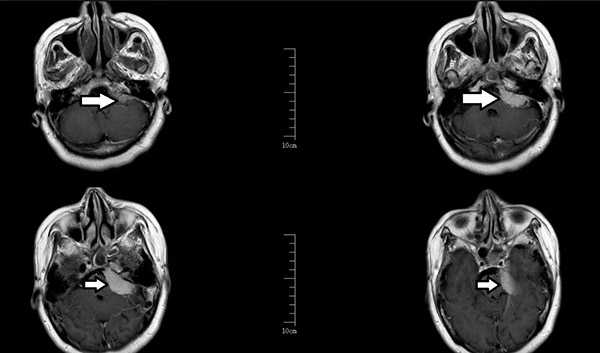

接诊的沈阳市第十人民医院(沈阳市胸科医院)神经中心景雪峰主任高度怀疑是三叉神经痛马上安排检查。核磁共振发现真相:李阿姨右耳后方的脑部"神经总闸"区--右侧桥脑小脑角区域发现占位性病变,藏着一颗乒乓球大的肿瘤。这里密布着:

术前增强磁共振